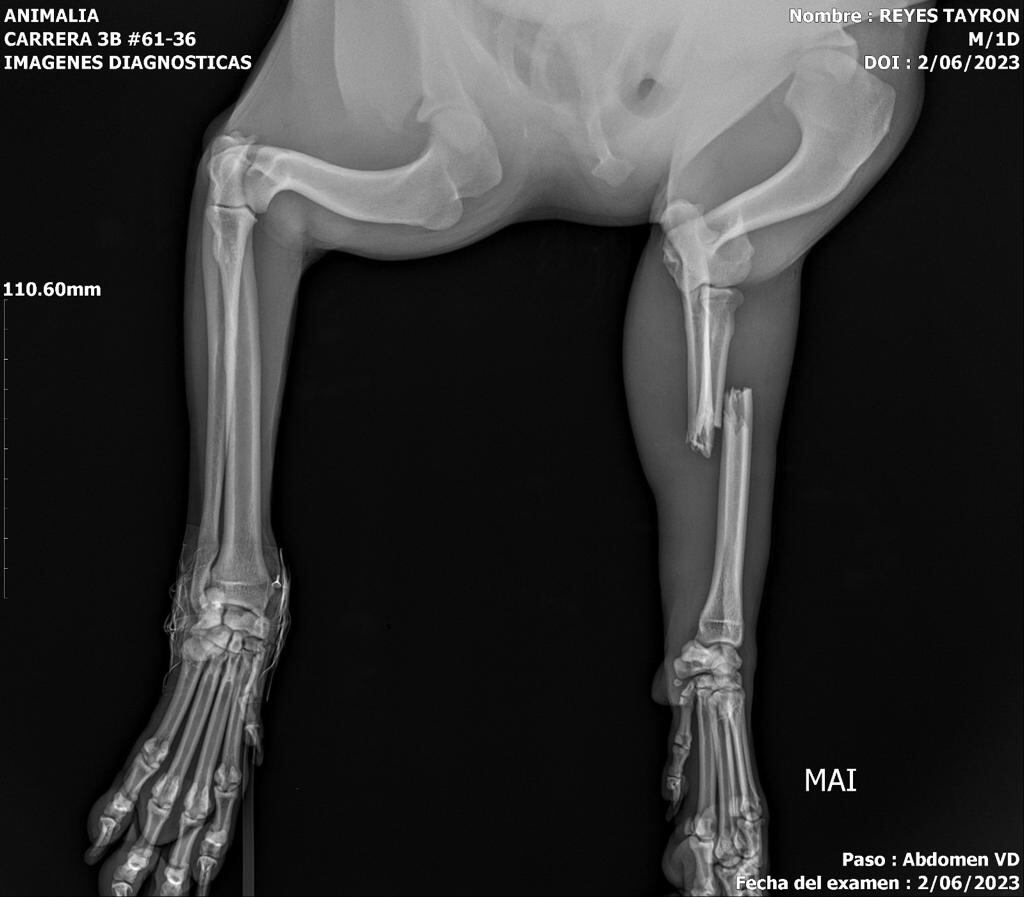

El 2 de julio de 2023, Tayron, un perrito criollo de aproximadamente 2 años, ingresó a una veterinaria en la localidad de Chapinero tras el reporte de su caída de la terraza en un tercer piso, causando la fractura de dos de sus patas.